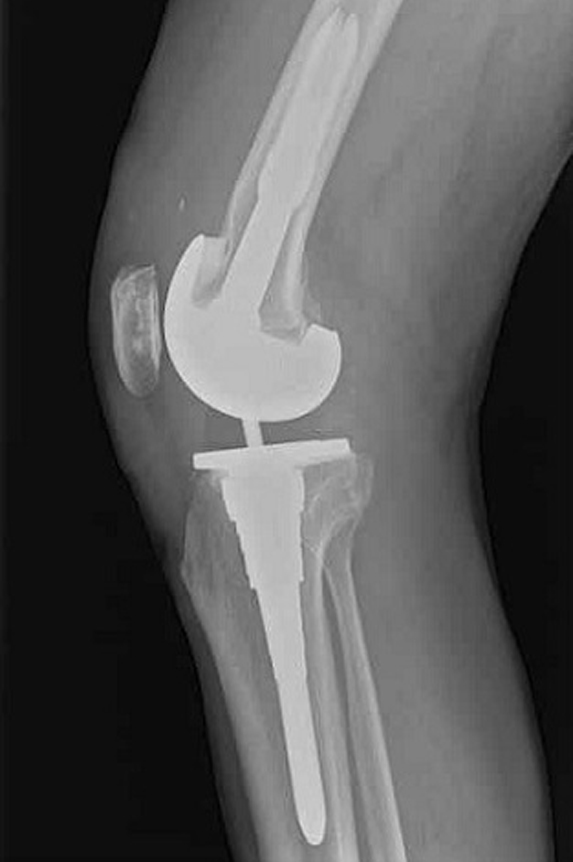

Revision Total Knee Replacement

Revision total knee replacement is the replacement of a failed total knee prosthesis with a new prosthesis. In simple terms, it is the replacement of a knee replacement or a "second knee replacement".

• How we do knee revision surgery?

First, the old implant is removed and,asses the condition of the bone and surrounding structures and conduct tests to make sure it is free from infection

We reassess for any bone loss if needed, autografts(taken from your own bone) or allograft (taken from the bone bank) are used to fill voids where bone has deteriorated.Most of the time we use metal augments, Then the new prosthesis is placed.

• Implants

As we follow American guidelines and techniques for our surgery.We always use USFDA approved implants imported from United States of America,Which are widely used worldwide for proven better results.